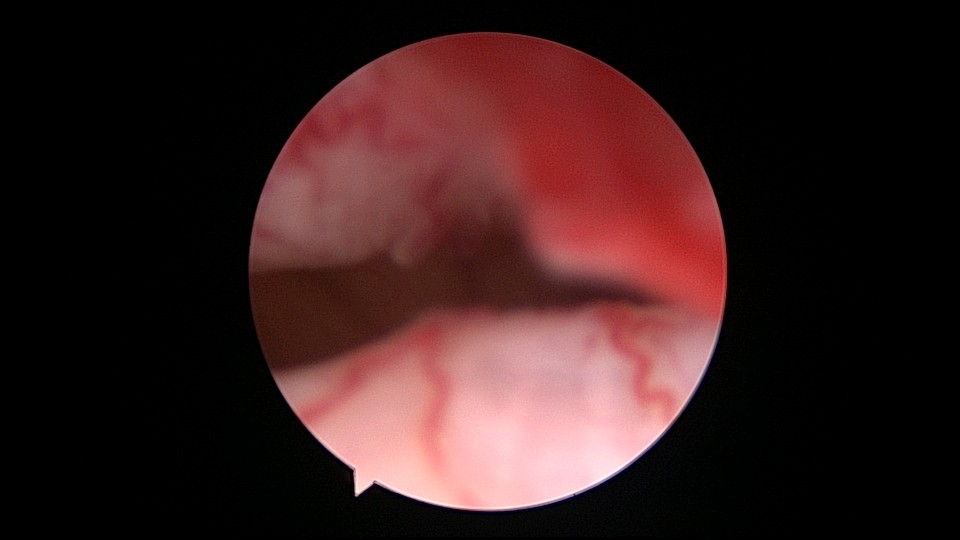

很有意思的一次取环经历:患者33岁,G2P1,剖宫产1次。安环7年,月经淋漓不尽3个月,2家医院取环失败,两次取环时间相隔24天,第二次取环失败后第二天到我院行宫腔镜取环。子宫后倾后屈位,剖宫产切口憩室处组织杂乱,爱母环位置正常,感觉是个比较简单的取环,取环钩探寻节育环,顺利取出。用刮匙准备诊刮,刮匙很容易进入,感觉很深,达13cm,但前面宫腔镜检查没有异常,以为是B超测量子宫有误,或者剖宫产粘连把子宫拉上去了,没有往子宫穿孔方面想,刮匙试探几次均是相同结果,试着刮了几下,没有内膜组织,再次置镜检查,结果镜子进入盆腔,看见网膜脂肪组织。宫颈内口闭塞,花了较多时间也进不去宫腔,穿孔处无出血,盆腔无积血,放弃诊刮。打电话给第二家取环医院的医生,得知前一天取环时感觉穿孔,放弃取环,介绍到我这里宫腔镜取环。分析整个过程,第一家医院在切口憩室处已穿孔,取环失败,穿孔处虽然愈合,却是一个薄弱环节,第二家医院和我们的宫腔镜均在该处进入盆腔,刮匙探查有底,是因为刮匙抵到了骶骨。